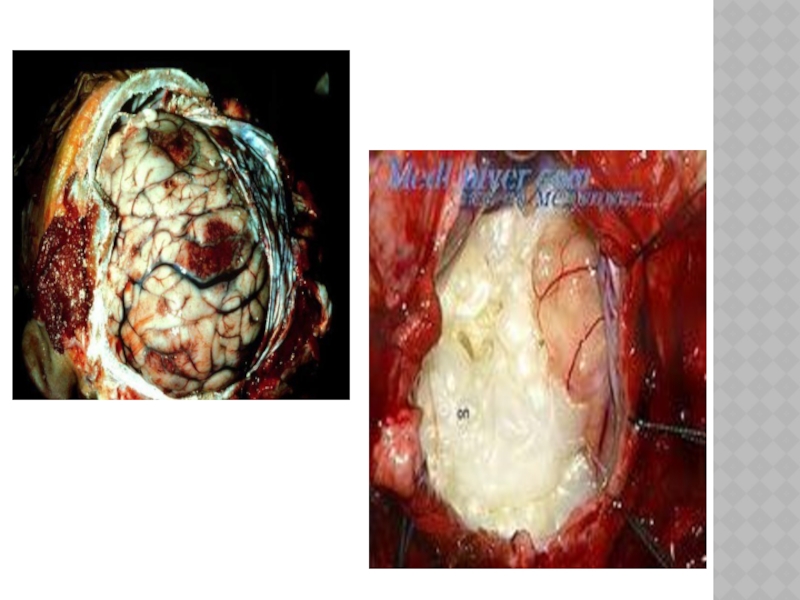

Слайд 131АБСЦЕСС ГОЛОВНОГО МОЗГА

Развивается при попадании микроорганизмов в мозговую ткань при открытом

ранении черепа, отите, пневмонии и других воспалительных процессах.

Слайд 132КЛИНИКА

протекают в две стадии:

1.Обнаруживаются симптомы, указывающие на наличие воспалительного

процесса (менингит, энцефалит), которые в процессе лечения уменьшаются или (реже) исчезают. 2.Мозговые симптомы, указывающие на внутричерепной объемный мозговой процесс+ признаки воспалительного процесса (лейкоцитоз в крови, ускоренное СОЭ, повышенное содержание белка и клеток в ликворе, повышение температуры).

Слайд 133ДИАГНОСТИКА.

Анамнез, данные состава ликвора, компьютерная томография.

Слайд 136ЛЕЧЕНИЕ

Хирургическое +антибиотики + сульфаниламиды